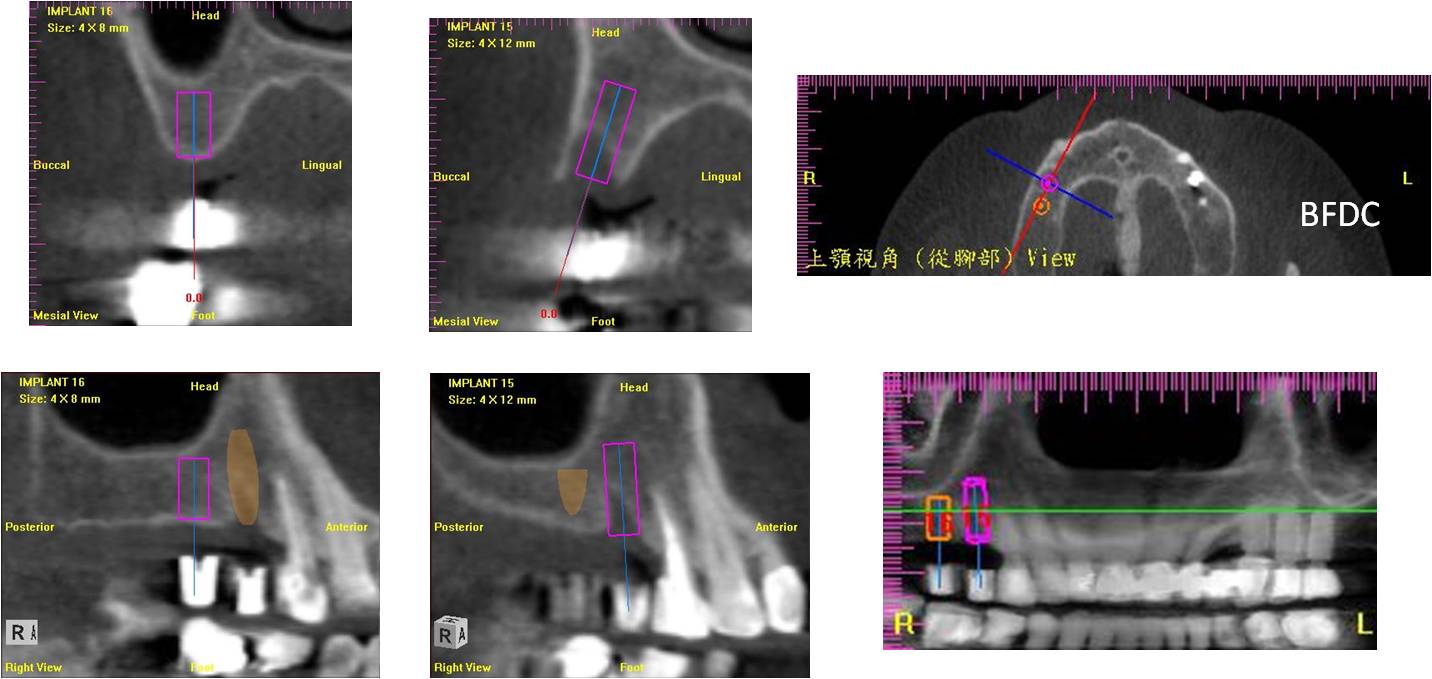

拔牙後6個月,電腦斷層評估